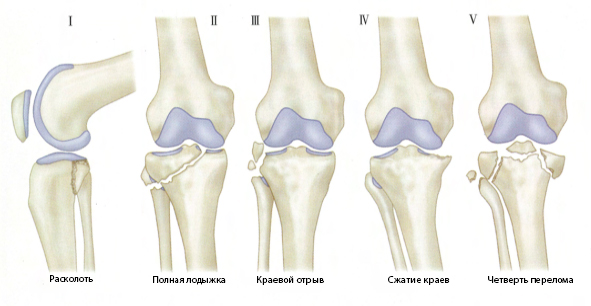

Для классификации типов переломов используется система классификации Шацкера:

Тип I:

Простой расщепленный перелом (рис. 1А): типичный клиновидный неоскольчатый перелом, фрагмент которого расщепляется и смещается латерально и вниз. Этот тип перелома часто встречается у молодых пациентов без остеопороза. При смещении для его фиксации можно использовать 2 поперечных спонгиозных винта.

Тип II:

Расщепленный и компрессионный перелом (рис. 1Б): латеральный клиновидный фрагмент кости расщепляется и отделяется, а поверхность сустава сжимается вниз и погружается в метафиз. Этот тип перелома часто встречается у пациентов пожилого возраста. Если компрессия превышает 5–8 мм или коленный сустав нестабильен, следует выполнить открытую репозицию. На метафиз следует поместить «целый» костный трансплантат для поднятия сжатой платформы и спонгиозный следует использовать винты и латеральную кору.Опорная стальная пластина зафиксирована.

Тип III:

Простой центральный компрессионный перелом (рис. 1C): простой компрессионный перелом суставной поверхности погружается в платформу, а латеральный кортикальный слой не поврежден. Это чаще встречается у пациентов с остеопорозом. Если компрессия сильная или подтверждена нестабильность сустава, следует использовать костную пластику для смягчения сжатой суставной поверхности и использовать опорные пластины для фиксации латерального кортикального слоя кости.

Тип IV:

Перелом медиального мыщелка (рис. 1D). Этот тип перелома может представлять собой простой клиновидный расщепленный, оскольчатый или компрессионный перелом медиального мыщелка, часто с вовлечением ости большеберцовой кости. Этот тип перелома имеет тенденцию к варусному отклонению под углом, поэтому следует выполнять открытую репозицию и использовать субхондральную фиксацию костным рафтом для уменьшения повреждения суставной поверхности с фиксацией стальной пластиной или без нее.

Тип В:

Двумыщелковый перелом (рис. 1E): расщепление плато большеберцовой кости с обеих сторон. Характеризуется тем, что метафиз и диафиз еще сохраняют свою непрерывность. Оба мыщелка можно фиксировать с помощью опорных пластин и спонгиозных винтов, чтобы избежать фиксации более крупными встроенными предметами. Мур, Пацакис и Харви провели ретроспективное исследование 988 пациентов с переломами плато большеберцовой кости, из которых у 296 были двумыщелковые переломы. Среди них в 95 случаях была выполнена открытая репозиция и внутренняя фиксация, и только в 11 случаях была выполнена как медиальная, так и латеральная фиксация пластиной. Раскрытие раны или инфицирование наблюдались в 9 из 11 случаев (82%). Кроме того, установлено, что 23% V-образных двумыщелковых переломов были инфицированы. Используйте небольшую противоскользящую стальную пластину, чтобы зафиксировать кончик перелома с меньшим расслоением мягких тканей.

Тип VI:

Платформенные переломы с разделением метафиза и диафиза (рис. 1F). Помимо одномыщелковых или двумыщелковых и суставных поверхностных переломов, встречаются также поперечные или косые переломы проксимального отдела большеберцовой кости. Из-за разделения диафиза и метафиза этот тип перелома не пригоден для тракционного лечения.Большинство переломов фиксируют опорными пластинами и спонгиозными винтами. Если оба мыщелка сломаны, необходима двусторонняя фиксация. Недавно некоторые ученые выступили за использование стальных штифтов и проволоки для фиксации этих сложных переломов.

Рисунок 1 Классификация переломов А. Тип I, простой расщепленный перелом, Б. Тип II, расщепленный перелом в сочетании с коллапсом, костная пластика в метафизарную пустоту для поднятия костного фрагмента для достижения репозиции и опорная стальная пластина для фиксации латеральной клиновидной формы костный фрагмент: тип C. III, простой центральный коллапсный перелом без наружного клиновидного костного фрагмента, при этом коллапс может быть спереди, сзади или вовлекать всю платформу. После разрушения костного трансплантата лучше всего добавить опорную стальную пластину для его защиты.Тип D.N, клиновидное расщепление медиального мыщелка, модельное расщепление медиального мыщелка (тип А, как показано на рисунке) или раздавливающий коллапс (тип B, на рисунке не показан), чаще встречается у пожилых пациентов с остеопорозом): тип E, V, плато большеберцовой кости расщеплено с обеих сторон. Обратите внимание на непрерывность между эпифизом и диафизом и поддерживайте его. Для двусторонней фиксации необходимо использовать стальные пластины Тип F, V, перелом характеризуется сухим Эпифиз отделен от диафиза, тип мыщелкового перелома неизвестен Могут встречаться все типы Проксимальный отдел большеберцовой кости следует фиксировать двусторонним опорные пластины.